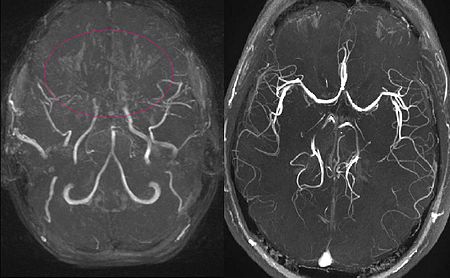

모야모야병은 뇌 기저부에 있는 주요 혈관이 점차 좁아지면서 뇌로 가는 혈류량이 줄어드는 질환입니다. 혈류가 부족해지면 뇌는 새로 가늘고 약한 혈관을 만들어 혈류를 보완하려고 하는데, 이 혈관들이 모여 있는 모습이 연기처럼 보여 ‘모야모야’라는 이름이 붙었습니다.